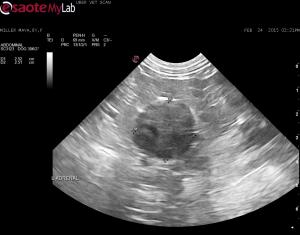

– a left adrenal mass (>2.5cm diameter) was detected that does not appear to be invading the renal blood vessels or the CVC (I followed the CVC from the right side in a cranial-caudal direction and flow was clean)

– I could not find a uterus or right ovary but found a structure caudal the left kidney that may be a left ovary?

What are your thoughts on the adrenal mass? Do you think the structure I am pointing to is a left ovary?